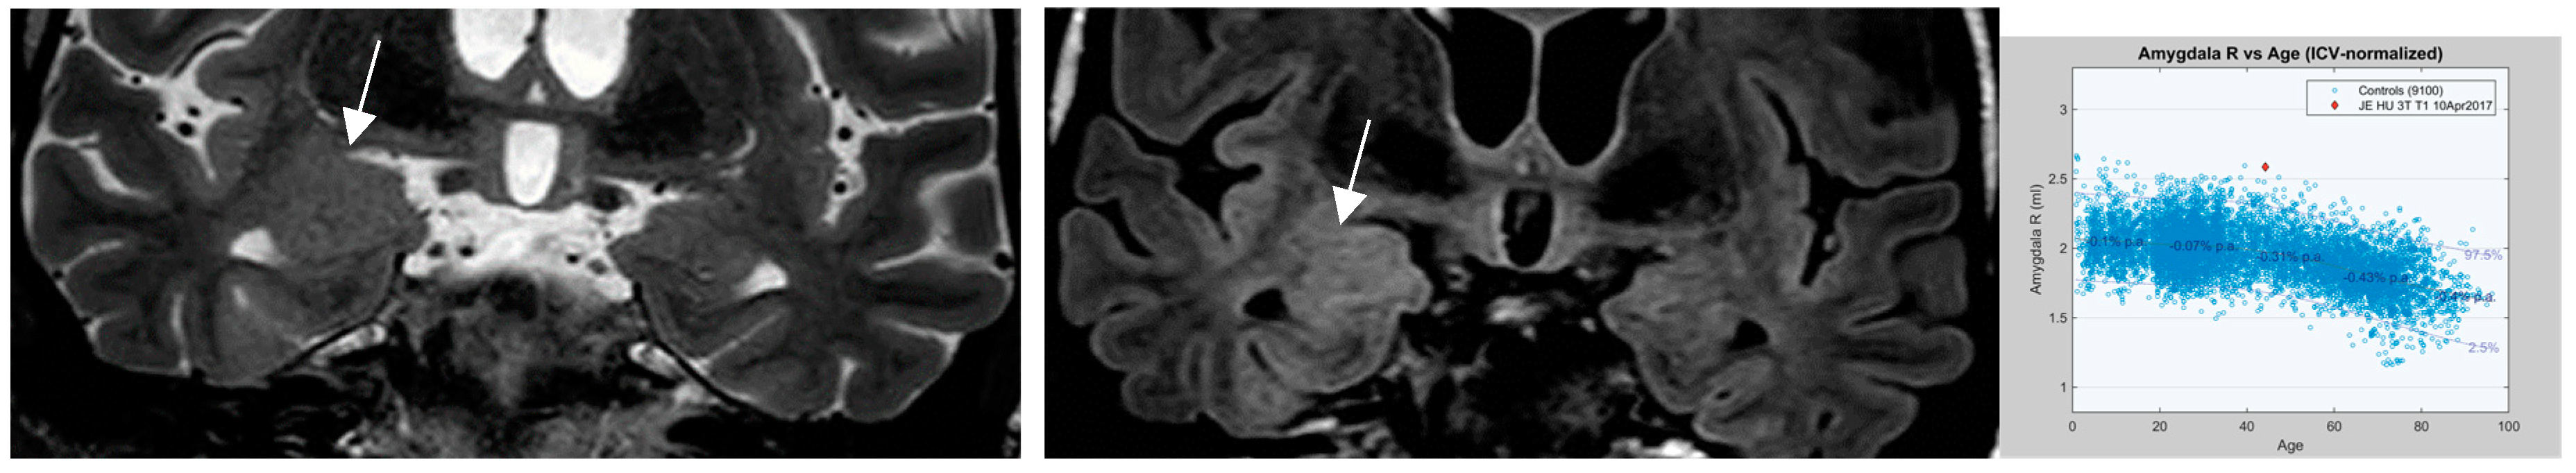

4.7. Postprocessing by Quantitative Analysis of Signal Intensity, Volumetry Enhances Temporal Lesion Identification

- Coan AC Morita ME, de Campos DM, Yassuda CL, Cendes F. Amygdala enlargement in patients with mesial temporal lobe epilepsy without hippocampal sclerosis. Front Neurol. 2013;4:166-170.

- Coan AC, Kubota B, Bergo FPG, Campos BM, Cende F. 3T MRI Quantification of Hippocampal Volume and Signal in Mesial Temporal Lobe Epilepsy Improves Detection of Hippocampal Sclerosis AJNR 2014; 35:77–88.